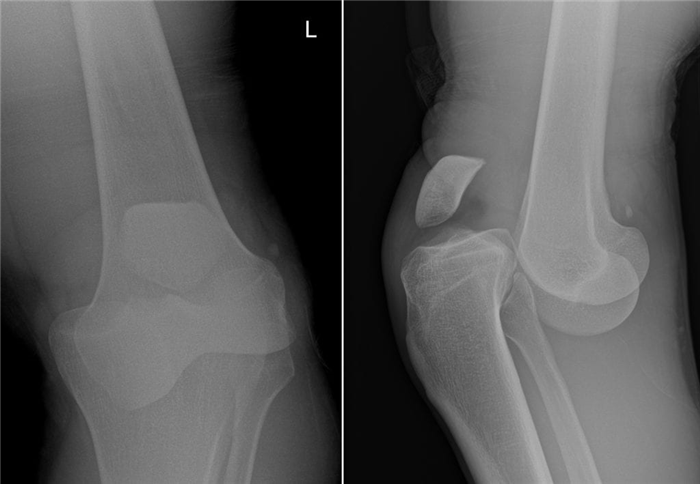

Мужчина 55 лет обратился с жалобами на боль, ограничение активных движений в правом плечевом суставе. Впервые травма в 1983 году, при заведении штанги за голову произошел вывих головки правой плечевой кости. В дальнейшем у больного было около 50 вывихов, которые пациент вправлял самостоятельно. Неоднократно обращался за помощью по месту жительства и в Киевский НИИТО в 2009-2010 гг., установлен диагноз: деформирующий артроз, хондроматоз правого плечевого сустава. Оперативное лечение не проводилось. В марте 2016 года проходил лечение в РНИИТО. При объективном осмотре определялась умеренная гипотрофия дельтовидной мышцы, а также мышц-ротаторов справа. Пальпация болезненна вокруг правого плечевого сустава. Движения резко ограниченны, с хрустом: отведение 25°, сгибание 30°, разгибание 20°, полное отсутствие ротационных движений. По данным рентгенографии правого плечевого сустава от 03.03.16 г.: деформирующий артроз III ст. с массой свободных тел в полости сустава (рис. 1).

Рис. 1. Рентгенограммы пациента при поступлении: снимок правого плечевого сустава в прямой проекции и аксиальной проекции (второй случай)

Рентгенография суставов - в области правого коленного сустава выявляются множественные, свободно располагающиеся в его полости, супрапателлярной сумке овальной и округлой формы образования (рис. 1). Рентгенснимки были проконсультированы с профессором И.В. Красицким. Высказано мнение о первичном остеохондроматозе. Больному предложено артроскопическое вмешательство, от которого он воздержался.

Однако рентгенографическая картина позволила кардинальным кардинальным образом изменить диагноз в пользу первичного синовиального остеохондроматоза правого коленного сустава. Данное профессором И.В. Красицким, на основании рентгенснимка, заключение об остеохондроматозе в наибольшей степени соответствовало именно данной клинической картине.